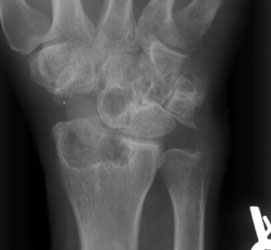

At the site of the implant, an inflammatory process occurs in response to

the foreign particles, which are sloughed off of the implant. This leads to

erosion of bone and articular cartilage, and intraosseous cystic changes.

There can also be soft tissue swelling and calcifications in the immediate

area. Fractures and destructive changes of the prosthesis are sometimes present.